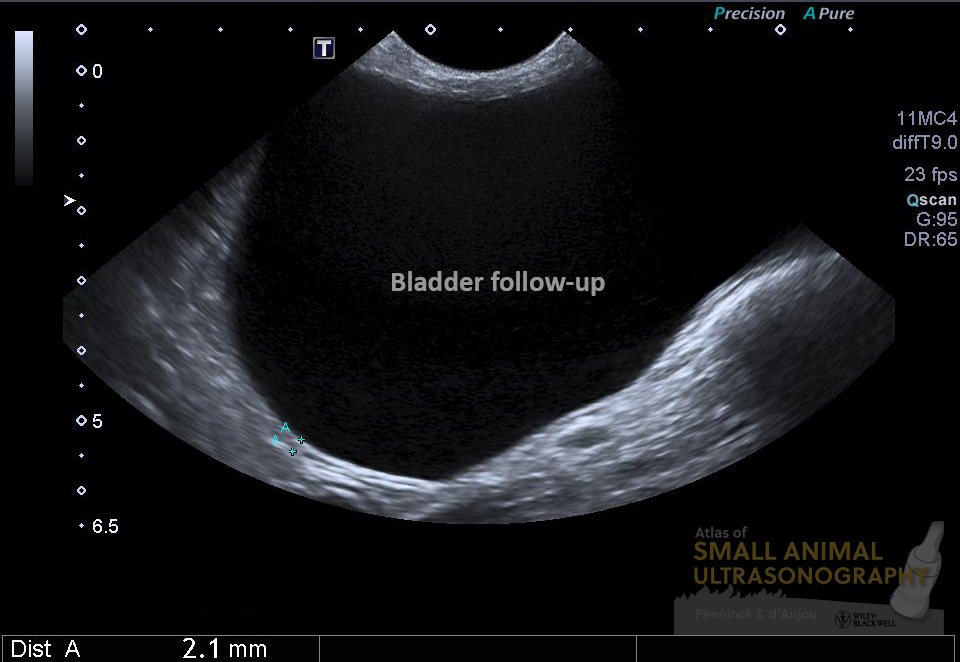

As we know however, the appearance of the bladder wall can be greatly influenced by the amount of luminal distension. And since that dog had been treated with several antibiotics and showed important signs of dysuria, an obstructive lesion remained suspected. It was suggested that a follow-up exam be formed with a full bladder. Here is what was seen on that second exam performed the following day…

The bladder wall was now smooth and normal in thickness. At the trigone, an irregularity was now detected and urethral wall thickening was now obvious. Ill-defined hyperechoic areas were also noted in the ventral urethral wall suggesting mineralization. These features are consistent with a transitional cell carcinoma, which was masked by the artifactual thickening of the bladder wall due to insufficient distension.